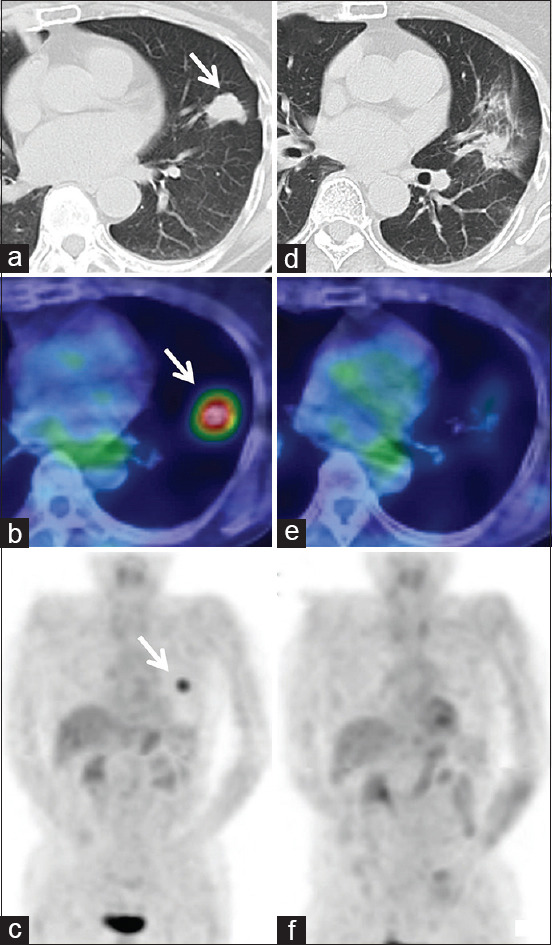

子宫内膜癌切除后10年以上发生单发肺转移是罕见的。然而,没有病例接受立体定向消融放疗(SABR)治疗孤立性肺转移,发生在切除后10年以上。一位76岁的女性,13年前有子宫内膜癌的病史,被诊断为子宫内膜癌转移的肺肿瘤。由于其他健康问题,患者不符合手术条件,而是接受了SABR。治疗耐受性良好,在SABR期间或SABR后2年内无不良事件报告。对于初始治疗后10年以上发生的子宫内膜癌肺转移,SABR可能被认为是一种安全有效的治疗选择。

Solitary lung metastases more than 10 years after the resection of endometrial carcinoma are a rare occurrence. However, no cases have undergone stereotactic ablative radiotherapy (SABR) for solitary lung metastasis that developed more than 10 years after resection. A 76-year-old woman with a history of endometrial carcinoma 13 years prior was diagnosed with a lung tumor that was confirmed to be a metastasis from the endometrial carcinoma. Due to other health issues, the patient was not eligible for surgery and instead underwent SABR. The treatment was well-tolerated and no adverse events were reported during or up to 2 years after SABR. SABR may be considered as a safe and effective treatment option for lung metastases of endometrial carcinoma that develop more than 10 years after the initial treatment.